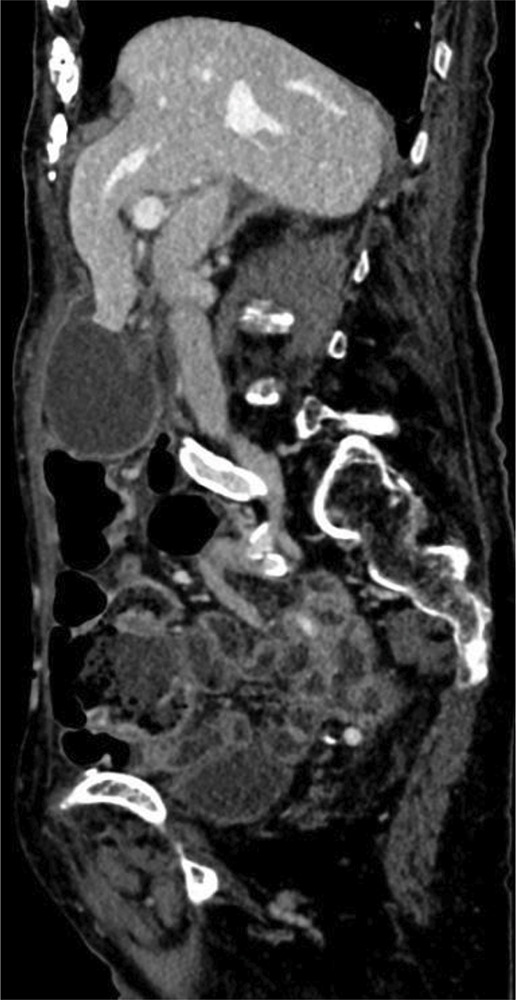

Teaching point: Gallbladder volvulus is a rare but serious diagnosis that needs urgent surgical treatment to avoid morbidity and mortality related to gallbladder ischemia and should be suspected in elderly female patients with acute right upper quadrant pain with imaging features including enlarged, abnormally positioned gallbladder and specific key findings on CT including "whirl sign" representing twisting of the cystic pedicle and "beak sign" at the gallbladder neck.

Abstract Image